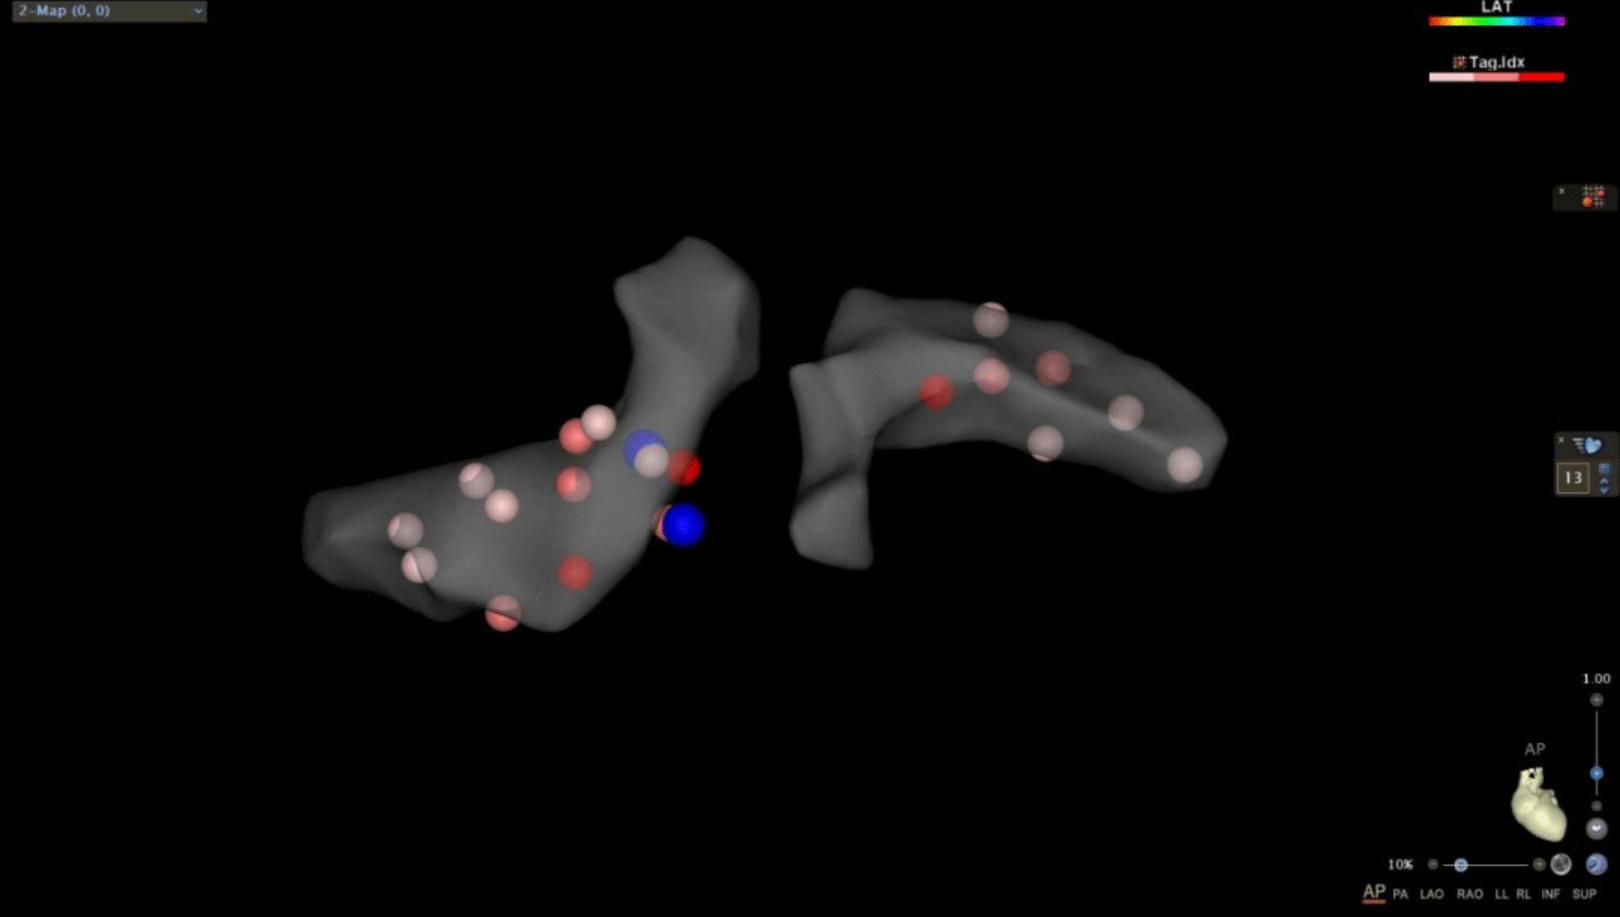

在充分考虑患者及其家属意愿后,汤宝鹏教授及李耀东教授经过术前讨论为患者量身定制了缜密的手术方案。手术由李耀东教授主刀采用导管微创介入手术,通过在X线下对左右肾动脉血管进行造影定位,同时在三维可视系统的指导下对肾动脉进行三维重建并进行射频消融。消融治疗通过在患者右腿植入一根直径大约2.5mm的管路进行,每次消融仅需30秒,18次治疗的手术过程约一个小时,且患者全程保持清醒,显著提升了患者的治疗体验。

(图为在三维可视系统下对肾动脉进行重建及消融治疗)